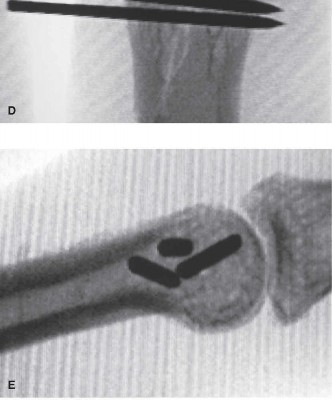

Clinical & Radiographic Imaging